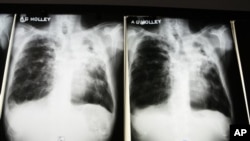

MDR-TB adalah penyakit yang kebal terhadap dua obat yang paling banyak digunakan dalam standar pengobatan TB. Sekitar 100 kasus MDR-TB di diagnosa setiap tahun di Amerika (foto: ilustrasi).

Sementara sekitar 100 kasus MDR-TB di diagnosa setiap tahun di Amerika, penyakit itu berdampak pada hampir setengah juta orang di seluruh dunia setiap tahunnya.